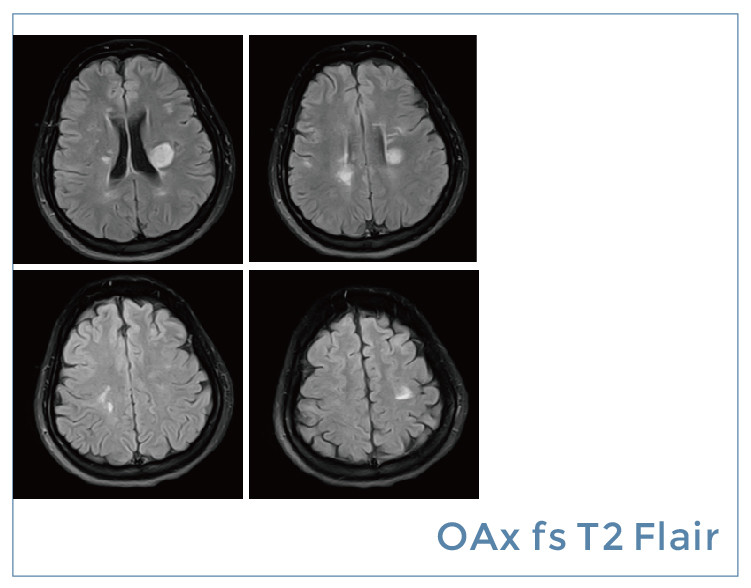

【朗润影像档案】20190823磁共振影像病例结果讨论